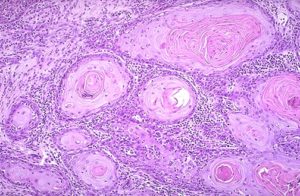

A pikkelyes méhnyakrák „rák gyöngy”

Amellett, hogy a nagy laboratóriumok szövettan végezzük immunhisztokémiai és molekuláris genetikai vizsgálatok. Ebben az esetben az értelmezés a biopszia eredménye megtalálható számokat, előtte a rövidítés CD, valamint a szavak, mint a citokeratin, vimentin, desmin, és mások. Értelmezésük már részt nőgyógyász.